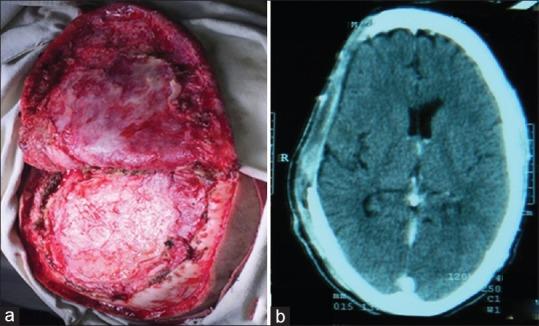

An extremely rare case of chronic epidural empyema after cranioplasty is presented. It derives its extreme rareness from its association with calcification. This patient when presented to our department had a complaint of swelling with on and off discharging sinus for 2 months adjacent to old incision scar mark. The patient had a history of decompressive craniectomy and evacuation of acute subdural hematoma, in some other institution, 8 years back. Following that, the patient underwent cranioplasty with the exteriorized and preserved bone flap. In the meantime, he was asymptomatic. It is a unique interesting case of chronic epidural empyema with calcified walls after 8 years of long duration following cranioplasty.

本文报告了1例颅骨成形术后极为罕见的慢性硬膜外积脓病例。其极端罕见性源于其与钙化的关联。该患者来我院就诊时,主诉在旧切口瘢痕附近出现肿胀,并伴有断断续续的窦道排脓2个月。患者8年前在其他机构有减压性颅骨切除术及急性硬膜下血肿清除术史。此后,患者接受了带外置保留骨瓣的颅骨成形术。在此期间,他没有症状。这是1例颅骨成形术后8年出现的具有钙化壁的慢性硬膜外积脓的独特有趣病例。